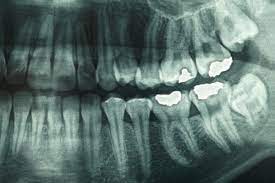

Blog from www.wrigleyvilledental.com